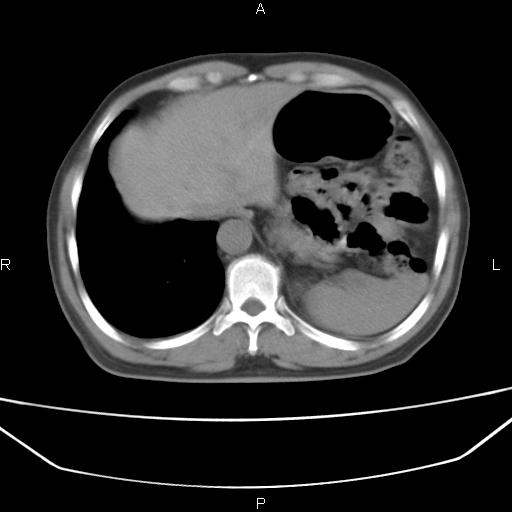

患者,男。50岁。近几日有咳嗽症状,无其他不适,既往病史无,考虑膈疝。请前辈们看看指导指导。

膈膨升,左下肺通气不良,膈肌好像还完整。

考虑左侧膈疝。

左侧膈疝。

符合隔膨升,膈肌较完整。